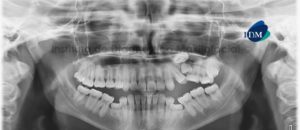

041 – Planificación y Tratamiento en Rehabilitación Oral con Prótesis sobre Implantes usando Análisis Cefalométrico

En los pacientes desdentados, que requieren una prótesis completa ya sea convencional o implanto soportada, los dientes artificiales se colocan en la prótesis completa por